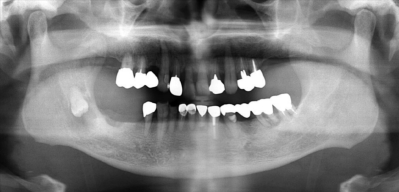

71歳の男性。顔面部の腫脹を主訴として来院した。右側顎下部に有痛性の腫脹を認める。初診時のエックス線写真、骨表示CT及び造影CTを示す。

顎下隙に認められるのはどれか。1つ選べ。